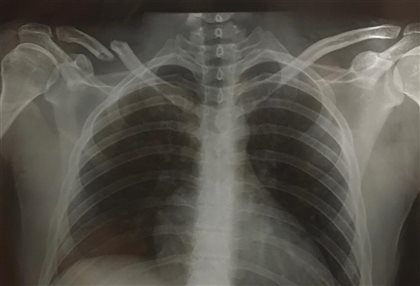

Al caer golpee con mi clavícula derecha en el asfalto y las pruebas en el hospital del circuito confirmaron la fractura.